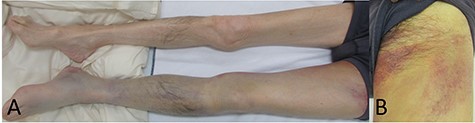

The patient looked pale but was conscious. He was thin and weighed 40 kg (body mass index, 14.5) due to loss of appetite after gastric surgery; however, his left thigh was reddish, edematous and painful (Fig. 1). Hemodynamics, such as blood pressure and heart rate, were stable. Blood tests revealed a hemoglobin level of 3.41 mmol/l. Ultrasonography showed a 72 × 52 mm PFAA with a thick thrombus and hematoma extending into the adductors (Fig. 2). A venous thrombus was also observed in the left femoral vein. Enhanced computed tomography (CT) revealed a ruptured left PFAA 64 × 54 mm in diameter (Fig. 3A and C). In addition, right iliac artery aneurysm and right CFA and SFA occlusion were also observed.

(A) The ultrasound image. The deltas point the PFAA. (B) Color Doppler imaging using ultrasonography. The deltas indicate the PFAA, and the arrows indicate the blood flow of the SFA.